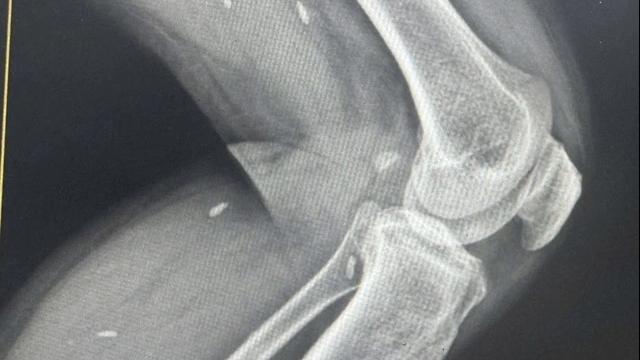

Bệnh nhân bị nhiễm độc sắt lâu ngày biểu hiện qua da - Ảnh: BSCC

Ông P.V.D (52 tuổi, ngụ tỉnh Lâm Đồng) đi khám bệnh da liễu vì trên mặt, cổ, sau gáy và lỗ tai có những mảng da dày sừng, màu xám đen.

Tại Bệnh viện Đại học Y dược TP.HCM, bệnh nhân được bác sĩ kiểm tra và ghi nhận da bị tăng sắc tố, các nang lông mọc sẩn sừng nhỏ li ti, mống mắt có quầng xanh.

Qua các xét nghiệm cho thấy bệnh nhân suy thận giai đoạn hai, phổi thâm nhiễm, men gan cao. Đồng thời, xét nghiệm sắt trong huyết thanh cho kết quả chỉ số cao bất thường. Bác sĩ kết luận, ông D. bị suy đa cơ quan do nhiễm độc sắt.